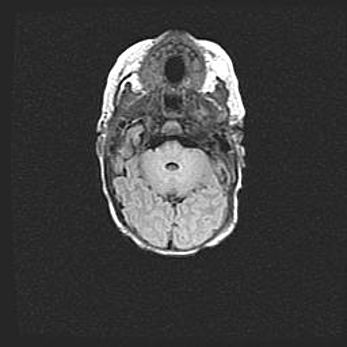

Мальформация Денди-Уокера. Киста задней черепной ямки.

Агенезия мозолистого тела.

Возраст: 2,5 месяца

Вес: 2420 г

Пол: женский

Окружность головы: 37 см

Срок гестации: 32 недели

Мальформация Денди—Уокера — редкий вид патологии ЦНС, представляющий собой врожденный порок развития каудального отдела ствола и червя мозжечка, ведущий к неполному раскрытию срединной (Мажанди) и латеральных (Лушка) апертур IV желудочка мозга. Для этогно синдрома характерна триада симптомов: гипотрофия червя мозжечка и/или полушарий мозжечка, кисты задней черепной ямки, гидроцефалия различной степени. В 70% случаев порок сочетается и с другими аномалиями головного мозга, в частности с агенезией мозолистого тела.